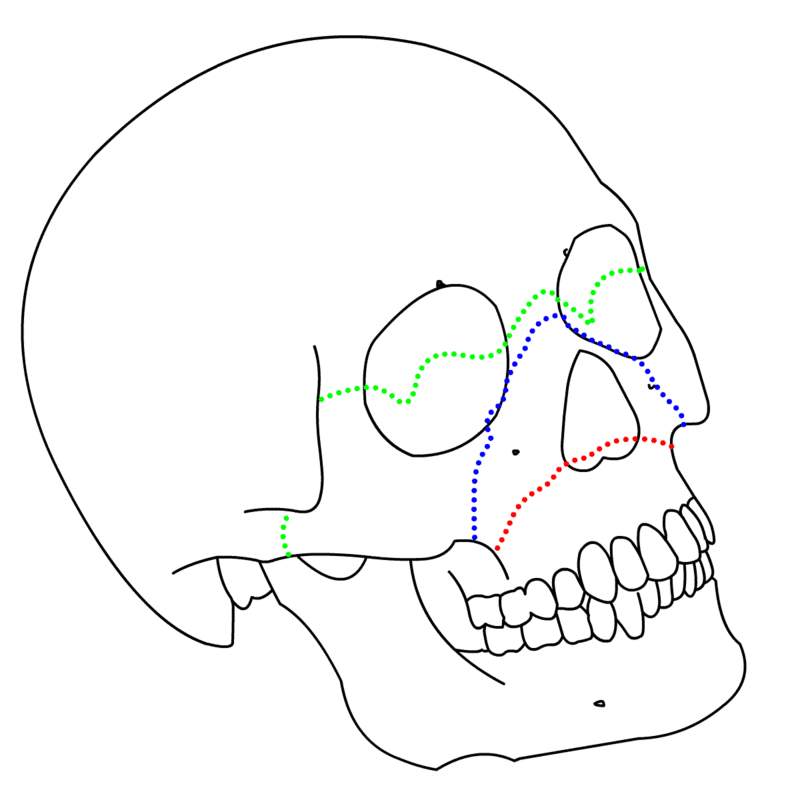

Facial Fractures

A diagram indicating 3 types of Facial fractures. The LeFort I (red), LeFort II (blue), and LeFort III (green) fractures